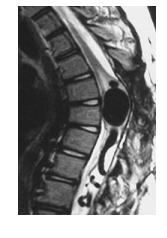

A 33-year-old presents with sudden onset neck pain. MRI is shown below. Which one of the following is most likely?

a. Cavernous angioma

Central nervous system (CNS) cavernomas are

rare vascular malformations consisting of closely

packed large sinusoid-like vascular channels with

little or no intervening nervous tissue. They can

occur anywhere in the CNS but favor the cerebral

hemisphere. Spinal cord cavernomas are uncommon, accounting for 3-5% of all cavernous malformations. Most commonly seen in the thoracic region (50%), they are uncommonly identified in the conus (10%); the cervical cord accounts for 40% of such lesions. Sudden onset paraplegia in a young adult. MR is the imaging modality of choice. The typical imaging features are of a well-defined lesion causing focal expansion of

the cord with mixed signal intensity on T1WI

and T2WI. These lesions are typically surrounded

by a complete hypointense rim owing to hemosiderin deposition. Typically, no or only sparse edema is associated with this lesion. Enhancement following contrast administration is variable.